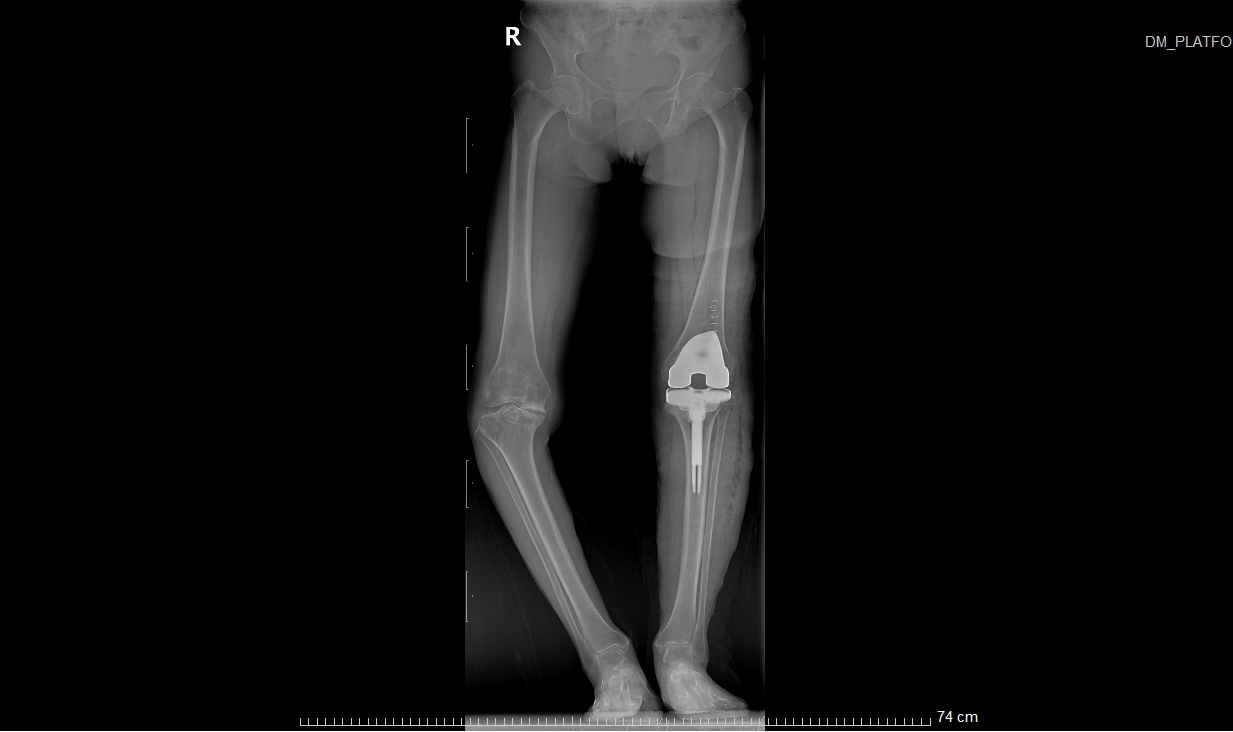

患者术后X光扫描

这个过程可以类比为镶牙,即切除受损部分并替换为金属材料。同理,在膝关节置换术中,医生会移除严重磨损的关节表面软骨及部分软骨下骨,在原位安装与原始膝关节表面形状类似的金属组件(即假体),使用骨水泥将假体与患者自身的股骨和胫骨固定在一起,使之恢复膝关节的正常功能。

患者术前VS术后对比